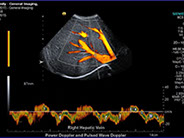

• Gefäßultraschall